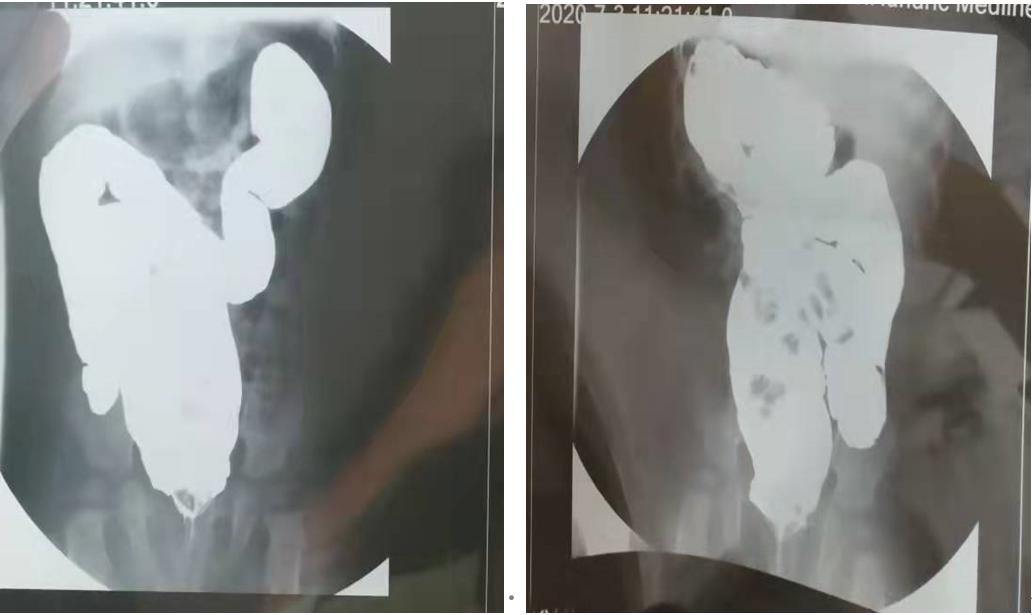

孩子生长发育尚可,腹部体检腹胀外无特殊表现,建议行钡剂灌肠检查。后检查结果如下图:

图示:乙状结肠冗长症(长度约45cm)结果出来后,孩子妈妈说:她也有结肠冗长症。

(1)首选X线钡剂灌肠:乙状结肠蜿蜒迂曲,呈环状甚至多环状,并突向右腹部,有的达肝下;长度符合诊断标准即可诊断。